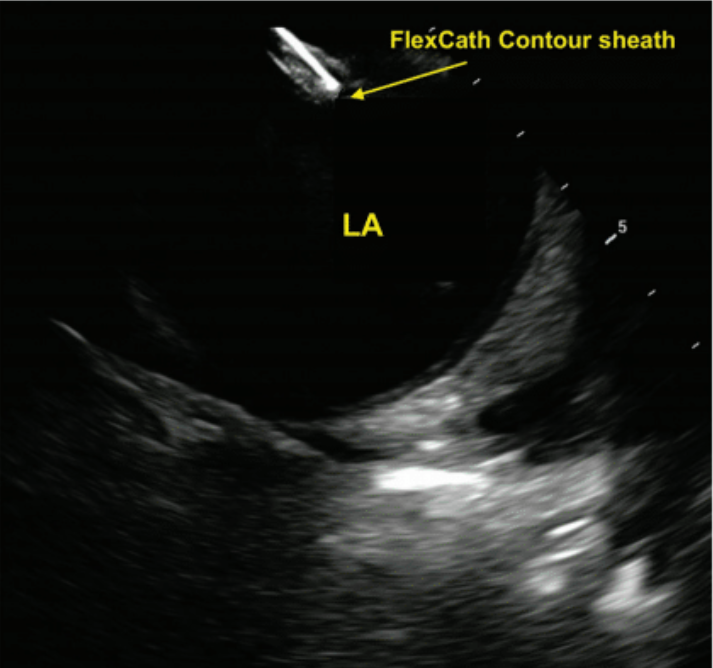

ICE was used to visualize the fossa ovalis and guide the transseptal puncture. A VersaCross RF transseptal wire (Boston Scientific) was used for transseptal access. The wire was advanced to the superior vena cava (SVC) through the short 10F sheath. The short sheath was then removed and a 10F FlexCath Contour sheath (Medtronic) and dilator assembly were advanced over the wire for zero-exchange transseptal access. The puncture was performed with real-time ICE imaging, ensuring accurate puncture without the need for fluoroscopic guidance. The transseptal assembly was withdrawn from the SVC down to the fossa. The sheath was manipulated to achieve tenting of the septum in a satisfactory location (Figure 4). Transseptal puncture was performed by delivering RF energy thorough the RF wire. The transseptal sheath was then advanced into the LA under continuous ICE monitoring (Figure 5).

LA=left atrium.